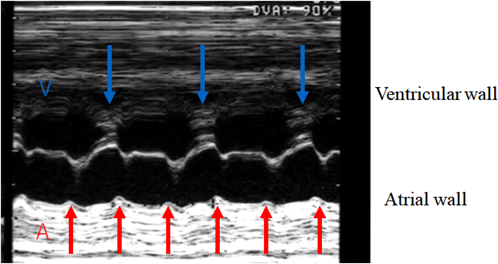

3) Evaluation of Ventricular Systolic Function

1. Fractional Shortening of the Ventricular Inner Diameter

Ventricular contractility is evaluated using the shortening rate of each ventricle. The cursor of the ultrasonography device is placed perpendicular to the septum beneath the AV valve in the 4CV. The movements of the mitral and the tricuspid valves are recorded simultaneously on M mode. This is helpful to identify systolic and diastolic phases. Fractional shortening (FS) is calculated with the difference between the end-diastolic and the end-systolic diameters of the ventricular cavity divided by the end-diastolic diameter.

FS=(end-diastolic inner diameter−end-systolic inner diameter)/end-diastolic inner diameter

The normal FS range (0.28–0.40) is independent of gestational age.90) If the position of a fetus renders the assessment of the ventricular size difficult, the modified Simpson method can be applied for determining the contraction rate tracing the ventricular cavity.91) Measurement errors, which could be rather large in fetal geometry, need attention when calculating FS whichever the methods are chosen.